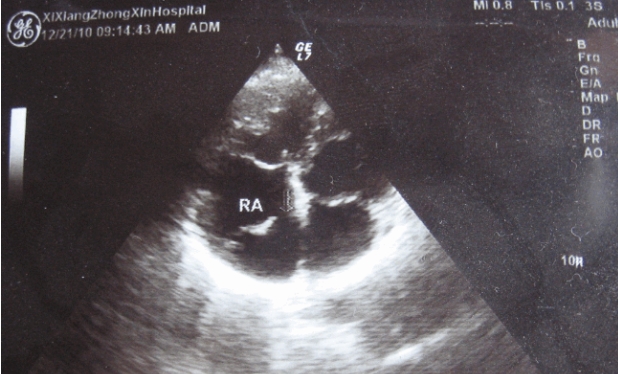

其实并不是单纯的黑白图像,而是由各种灰度值构成的。在彩超中,不同的灰度值代表了不同的声强信号,也就是不同的回声强度,而这些回声强度的差异则反映了人体内部组织的密度、形态等特征。彩超是一种利用超声波进行无创检测的医疗技术,其原理是通过超声波在人体内部产生回声,然后利用电子学技术将这些回声转化为图像。通过颜色变化来反映不同组织或血流的速度和方向,从而帮助医生进行诊断。

那么为什么彩超不能直接输出彩色图像呢?这是因为彩色图像需要RGB三种颜色通道来表示,而彩超只有单色超声波发射器和接收器。为了实现彩色显示,必须对超声波信号进行频率分离和处理,即把超声信号分成许多不同的频率,然后通过计算得出不同频率的回声强度,并将其映射至RGB颜色空间中。

这也就是彩超中Color Doppler技术的实现原理,通过对超声波信号进行多普勒频移分析,即将回声信号中因血液流动而引起的频率变化(多普勒效应)提取出来,从而反映出血液的流速和流向,并将其在图像上以不同颜色的形式呈现出来。